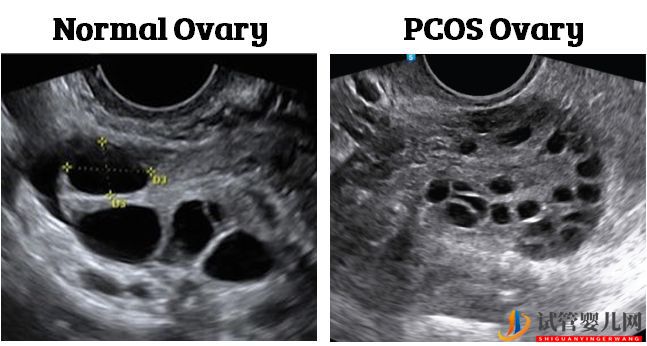

多囊卵巢綜合癥通常由(El Hayek等人,2016)診斷。

高雄激素癥(男性性激素如睪酮的分泌增加月經周期不規律多囊卵巢(通過超聲測量),其特點是有許多小卵泡

在多囊卵巢綜合癥中,較高的雄性激素水平破壞了參與卵泡發育的激素平衡。這導致了大量較小的、發育不良的卵泡(Dumesic等人,2008年)。

這些較小的卵泡可能不會以同樣的速度發育,這可能會影響質量。Chen等人(2008年)發現,患有多囊卵巢綜合癥的婦女有。